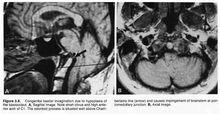

Chamberlain線目的通過影像學測量方法分析延髓頸髓角(cervicomedullary angle,CMA)與齒狀突超出Chamberlain線高度(the height above the Chamberlain line of the odontoid,H)的內在關係。方法蒐集自2009年1月—2011年11月底的鄭州大學第一附屬醫院收治的顱底凹陷症患者的影像學資料,根據病例入選標準共有38例入選,分別在其頸椎平片上測量其齒狀突超出Chamberlain線高度,在其MRI正中矢狀位上測量延髓頸髓角。結果顱底凹陷患者的延髓頸髓角與齒狀突超出錢氏線高度呈顯著的線性相關關係,回歸直線方程為CMA=-1.78*H+148.233,決定係數r=-0.481,係數部分P=0.002,常數部分P0.001。該回歸直線方程有統計學意義。結論顱底凹陷患者的延髓頸髓角隨著齒狀突超出錢氏線高度增加而呈下降趨勢,故枕頸融合術治療顱底凹陷時復位上移的齒狀突可明顯解除延髓頸髓交界區水平的壓迫。